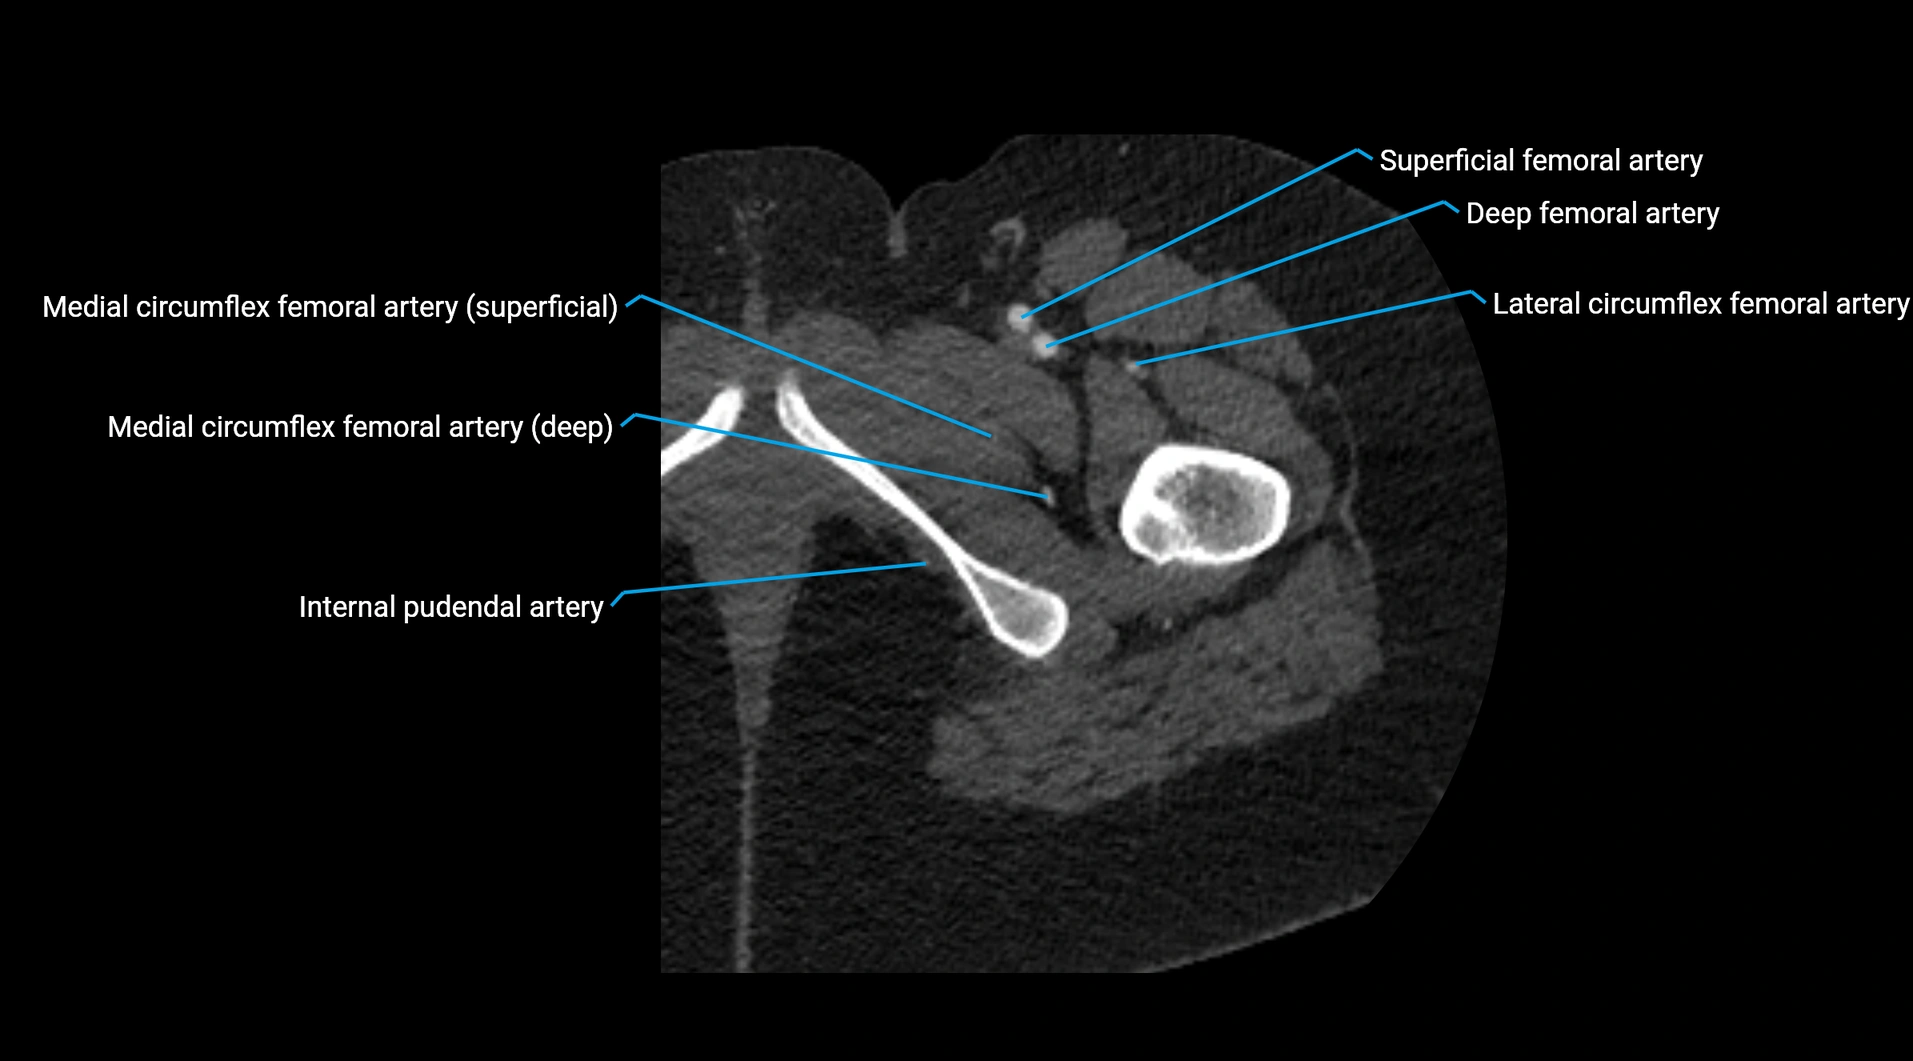

CT images

image